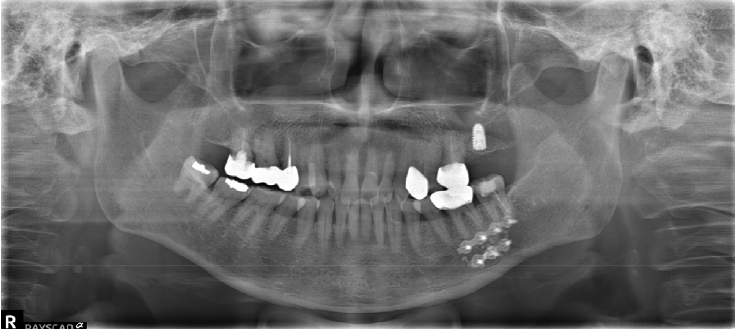

Case 5

A 73-year-old male was referred after endodontic treatment of the mandibular right second molar (#47) with severe post-treatment pain. Evidence of Calcipex II extrusion into the IAN canal was evident on the panoramic radiograph and CBCT. (Fig. 8). Root canal treatment was done about 2 months ago. He underwent foreign body removal under general anesthesia (Fig. 9). Postoperatively, he reported minimal change in numbness symptoms. He was lost to follow-up but returned six months later complaining of recurrent neuropathic symptoms and itching. Carbamazepine was prescribed. No follow-up sensory testing was performed.